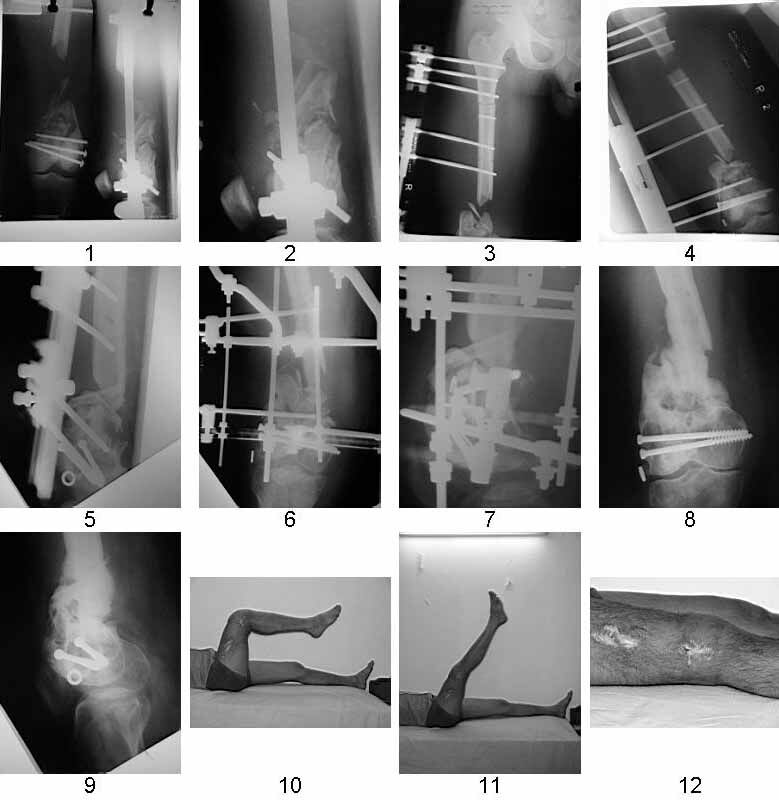

dear MAGDY we have treated exactly similar case intially with debridement & ILIZAROV ring fixator by end of three months patient had exuberent callus along whole length of left out periosteal sleeve &fixator was removed walking spica was applied, unfortunately after one month in spica he developed break in the bridging bone and now we have treated him with locking plate &bone graft one month back and on CPM machine with knee movement of 90 deg.

There are 3 main options:

1 Ilizarov bone transport

2 Vascular fibular graft+plating

3 Diaphyseal endoprosthesis - see photo (dangerous in soft tissue loss and infection)

Similar case.

They do well with bone transport.

I do an acute or accelerated shortening to reduce the gap as much as proximal, and distract proximally to restore length.

In this particular case, notice the change of fixator - orthofix type of unilateral fixator worked well initially but did not allow me to compress beyond a point, which is when I changed to an ilizarov for further compression at the gap/nonunion site.